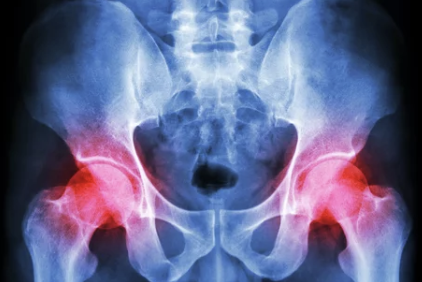

고관절 통증 증상: 원인과 치료 방법, 예방까지 자세히 알아보기

고관절은 골반과 허벅지뼈를 연결하는 관절로, 우리 몸의 움직임과 균형을 책임지는 중요한 역할을 합니다. 하지만 다양한 원인으로 인해 고관절 통증이 발생할 수 있으며, 이는 일상생활에 큰 불편을 줄 수 있습니다. 이번 글에서는 고관절 통증의 증상, 원인, 치료 방법, 예방 팁 등을 자세히 다뤄보겠습니다.

고관절 통증은 골반과 대퇴골(허벅지뼈)이 연결된 부위에 발생하는 통증으로, 고관절 내부뿐 아니라 주변 근육, 인대, 신경 등 다양한 부위에서 유발될 수 있습니다.

- X-ray: 골절, 관절염 등 뼈 문제를 확인.